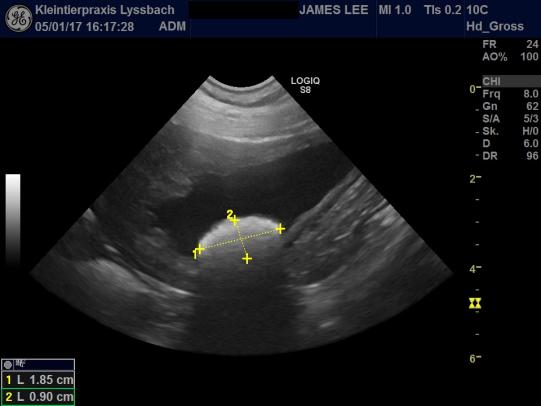

Der liebenswürdige Rüde lässt sich gut untersuchen - äusserlich ist der Hund unauffällig. Im Ultrsachall zeigt sich jedoch, dass sich der Blasenstein seit der letzten Kontrolle keineswegs verkleinert hat - mit gut 2 cm Durchmesser ist er sogar noch etwas grösser als bei der letzten Kontrolle.